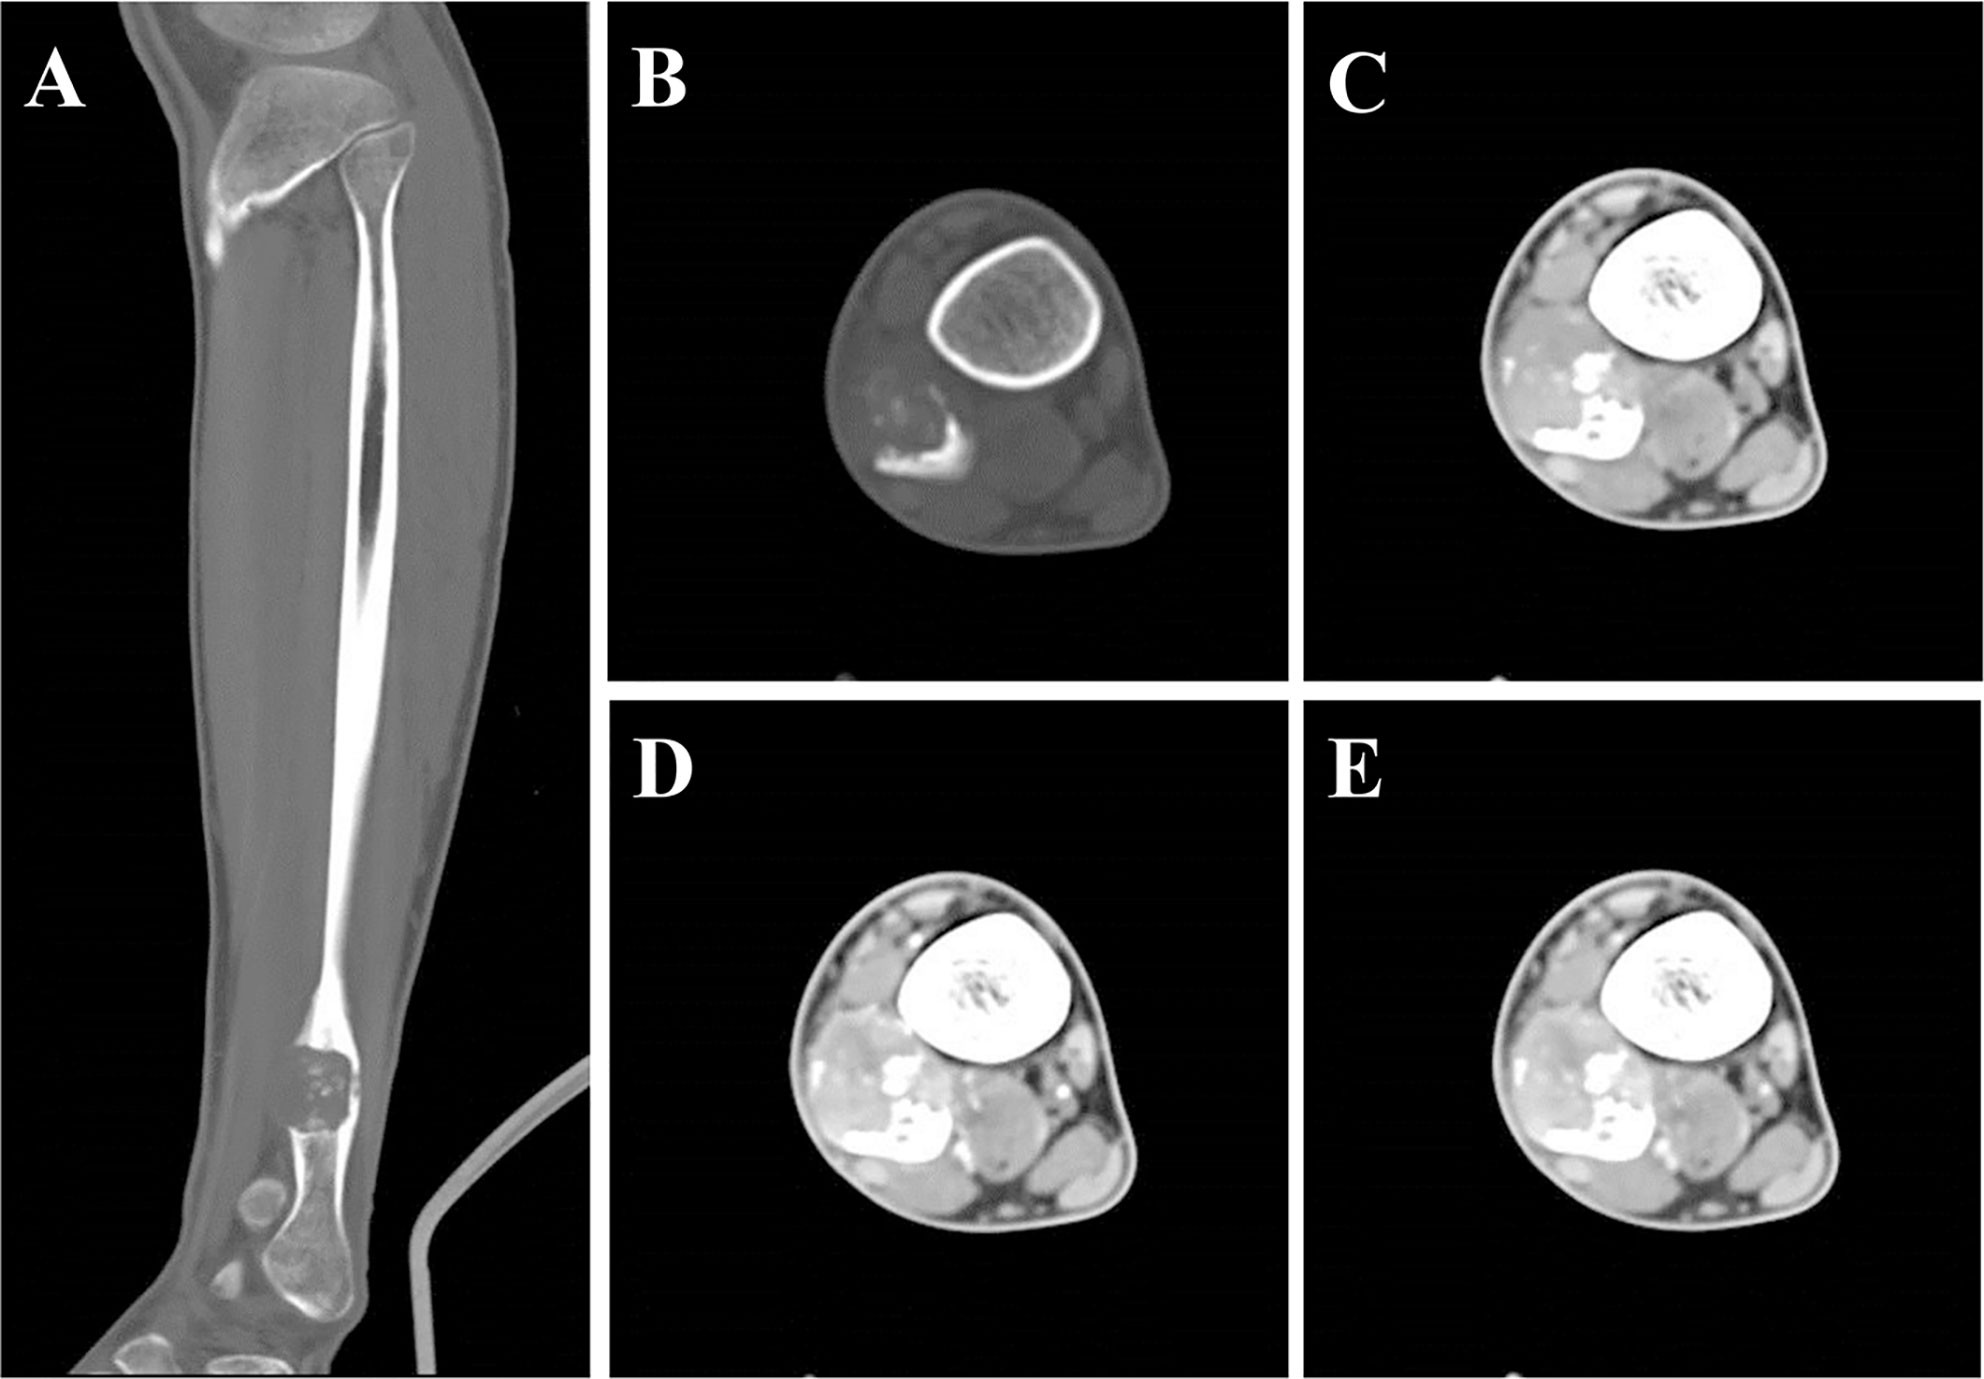

Plain X-ray revealed an irregular, low-density and well-demarcated region of bone destruction in the right distal fibula with scattered patches of slightly high density inside and slight periosteal reaction. Slight swelling change of the adjacent soft tissue was also observed. Computed tomography (CT) images of bony window showed centrally expansile osteolytic changes with scattered punctate bony sclerosis inside (Figures 1A, B). Axial CT images demonstrated a soft tissue mass with heterogeneous density (Figure 1C) and mild enhancement in the arterial phase (Figure 1D) and moderate enhancement in the venous phase (Figure 1E). There were no signs of fibular artery, venous, or small saphenous venous invasion. Magnetic resonance imaging (MRI) revealed a focal, 2.5cm × 3.0 cm × 3.2 cm, hypo- and isointense mixed mass on T1-weighted images (T1WI) (Figure 2A), and hypo- and hyperintense mixed mass on T2-weighted images (T2WI) (Figure 2B). There were no signs of necrosis, hemorrhage, or cyst formation within the mass. However, adjacent soft tissue edema and swelling was seen. Gadolinium-enhanced T1WI revealed obvious perilesional enhancement, particularly in the region adjacent to the normal tissue (Figures 2C–E). The MRI report suggested an osseous malignant tumor in the right distal fibula.

Figure 1 CT showed a lesion of bone destruction in the right distal fibula. Sagittal (A) and axial (B) CT of bony window showed a centrally osteolytic lesion with an expansive growth pattern, scattered punctate bony sclerosis inside and a local, slight periosteal reaction. Axial CT of soft tissue window images demonstrate a well-demarcated soft tissue mass displayed uneven density in unenhanced phase (C, CT value = 93 HU) and mild enhancement in the arterial phase (D, CT value = 113 HU) and moderate heterogeneous enhancement in the portal phase (E, CT value = 123 HU).